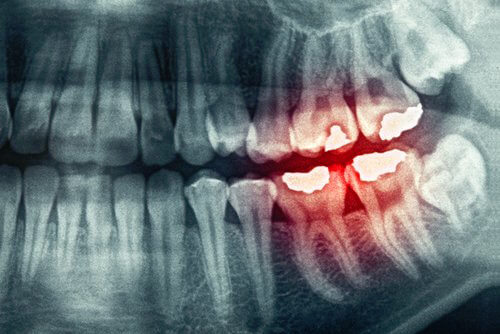

1. Bruxisme

Le bruxisme est un problème qui affecte plus de gens que nous le pensons. Il consiste à serrer les dents ou les mâchoires. Dans les cas les plus extrêmes, une attelle de décharge est habituellement utilisée. Si elle n’est pas utilisée, cela peut causer une usure importante des dents.

La tension qui se manifeste lorsque vous serrez la mâchoire vous fera mal à la tête le matin. Ceci est le résultat du stress, de l’inquiétude, de l’anxiété ou de la dépression. Parfois, même l’utilisation d’une attelle ne nous empêche pas d’avoir mal à la tête.

L’idéal dans ces cas est non seulement de consulter un dentiste qui nous fournit une attelle qui protège nos dents, mais aussi un psychologue. Il est important de savoir d’où vient toute la tension, ce à quoi nous pensons la nuit en grinçant des dents.